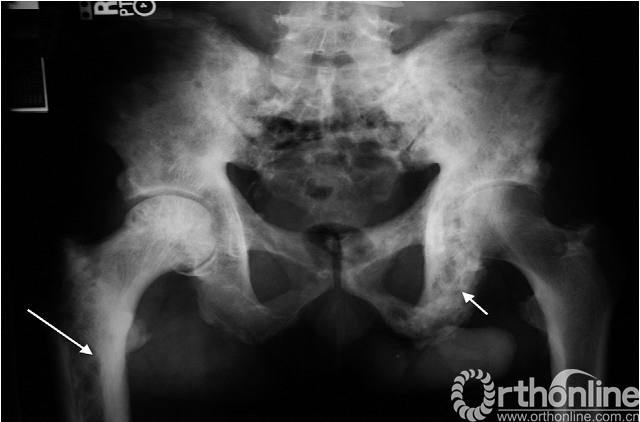

临床表现:佩吉特病被认为是一种多发性的骨疾病,最常见于骨盆。通常无症状、偶然被发现,但也可表现为与活动无关的钝痛。40岁以下罕见,但50岁以上发病率高达3%〜4%。病因不明,但有间接证据表明可能与感染有关。长期的疾病可导致骨畸形、病理性骨折及骨肉瘤(少见)。

影像学特点:佩吉特病有典型的X线表现,粗大的骨小梁,增厚的骨皮质及病变骨直径的增大(图11)。疾病的进展典型的表现为先溶骨性改变后发展为成骨性改变,但大部分是混杂在一起同时进行的。在脊柱侧位片上,椎体四面的骨皮质增厚形成“相框”样外观改变。负重的下肢骨骼,特别是胫骨,在长期病变过程中可能导致弯曲畸形(图12)。

图11. 骨盆佩吉特病,骨盆和股骨近端弥漫性受累,表现为骨小梁粗大,坐骨直径增加(短箭头)和皮质增厚(长箭头)。